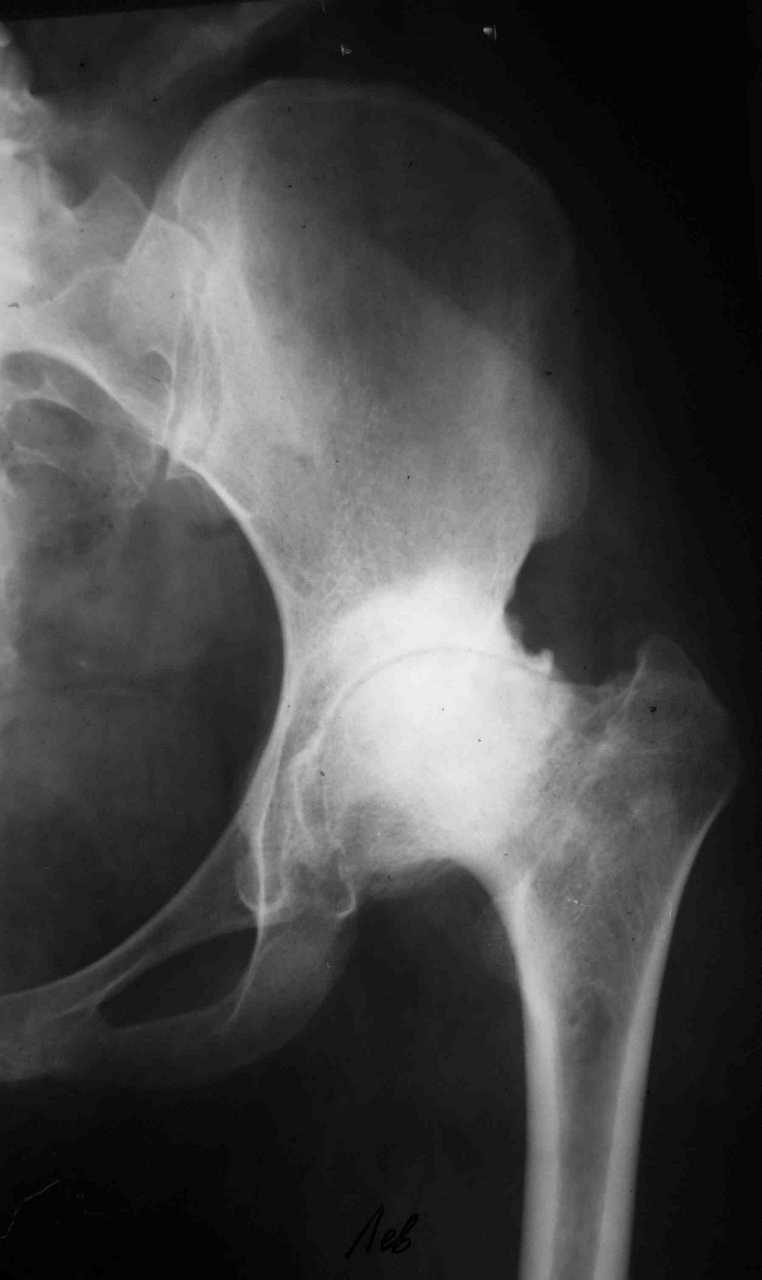

В настоящее время нет возможности сделать осевые снимки всей конечности. Это всё чем я раполагаю на сегодняшний день.

Спасибо. Картина несколько прояснилась. А планов в отношении тазобедренного сустава нет? Или пациентку беспокоит только колено.

Пациентку беспокоит только выраженный болевой синдром в коленном суставе.